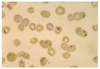

Thin walled sporulated sporocyst in fecal float

All mammals

DMSO carbol fuschin stain

Cryptosporidium parvum

Pink stained oocysts

Small oocysts

4-8 naked sporozoites in fresh feces = NO sporocyst

Does not need to sporulated to be infective